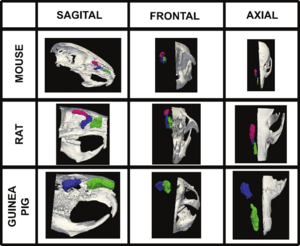

Publication: Front Zool. 2015 Dec 1;12:33. PMID: 26628903 | PDF Authors: Young R, Maga AM. Institution: Center for Developmental Biology and Regenerative Medicine, Seattle Children's Research Institute, Seattle, WA, USA. Background/Purpose: Here we present an application of advanced registration and atlas building framework DRAMMS to the automated annotation of mouse mandibles through a series of tests using single and multi-atlas segmentation paradigms and compare the outcomes to the current gold standard, manual annotation. Results: Our results showed multi-atlas annotation procedure yields landmark precisions within the human observer error range. The mean shape estimates from gold standard and multi-atlas annotation procedure were statistically indistinguishable for both Euclidean Distance Matrix Analysis (mean form matrix) and Generalized Procrustes Analysis (Goodall F-test). Further research needs to be done to validate the consistency of variance-covariance matrix estimates from both methods with larger sample sizes. Conclusion: Multi-atlas annotation procedure shows promise as a framework to facilitate truly high-throughput phenomic analyses by channeling investigators efforts to annotate only a small portion of their datasets. Funding:

Visualization of the distances between the atlas surface that was landmarked (p90) and four other surfaces constructed. a 50 % Probability surface (p50); b 70 % Probability surface (p70); c Surface thresholded at grayscale value of 35. d Surface thresholded at grayscale value of 55. RMS: Root mean square error. Segmented left hemi-mandibles were imported into 3D Slicer and visualized using a fixed rendering and threshold setting. |